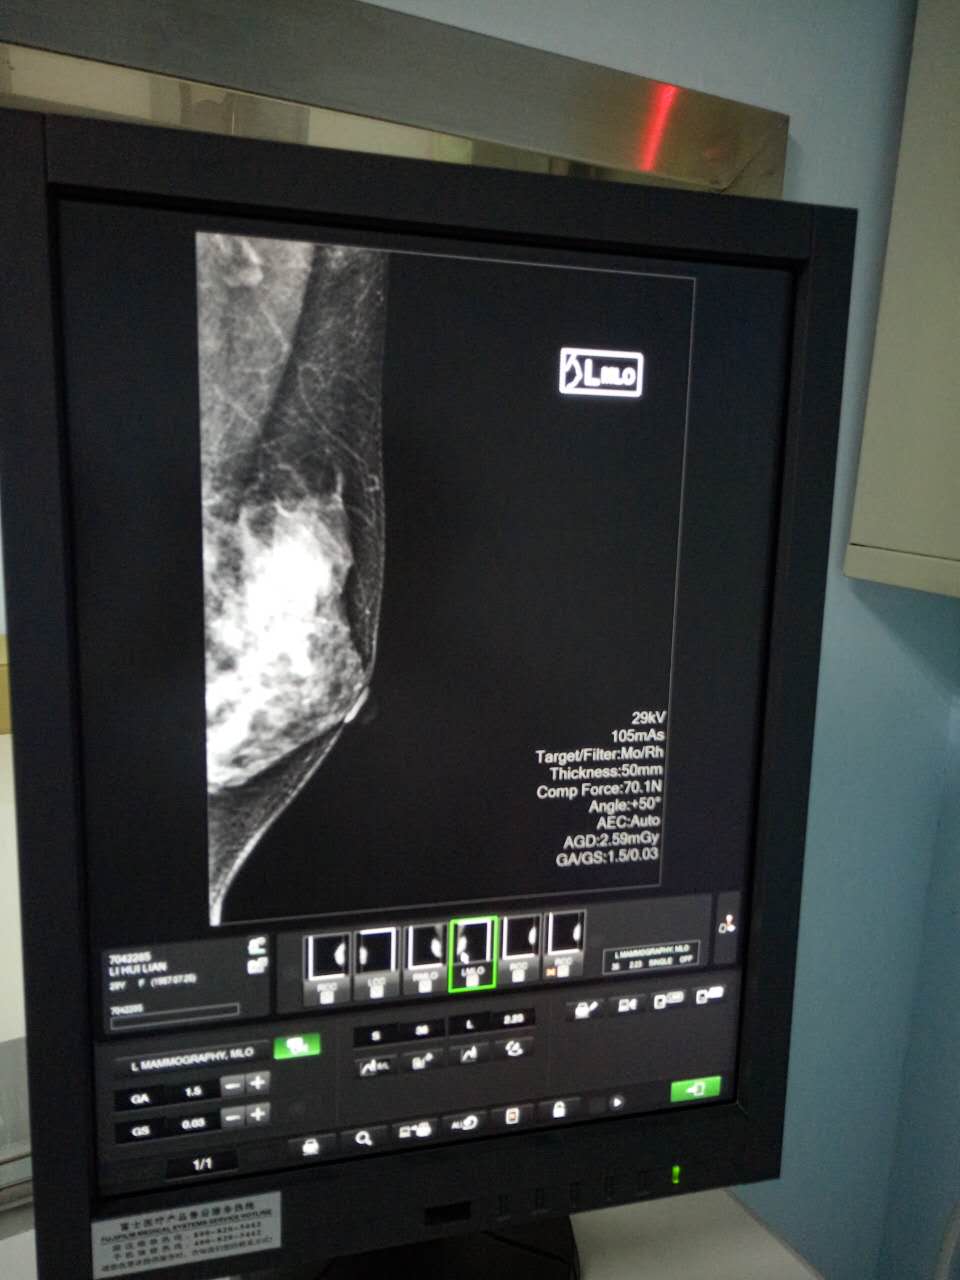

7月27日,海南西部中心医院第一台数字化乳腺X线机(又称乳腺钼靶)在该院东病区(新区)投入使用,填补了该院乳腺X线检查的空白,使乳腺病变的人群普查成为可能。

据该院放射科主任、主任医师李岩介绍,乳腺钼靶是一种专门用于乳腺病变检查的设备,它通过低剂量软X线拍摄乳腺,能清晰显示乳腺各层组织,可以发现乳腺增生、各种良恶性肿廇及乳腺组织结构紊乱,可观察到小于0.1毫米的微小钙化点及钙化簇,对于临床不可触及的以微小钙化簇为唯一表现的早期乳腺癌,具有特征性的诊断意义。该检查具有全面、直观、操作简单、安全和费用低廉等特点,是目前早期乳腺癌筛查的有效手段。